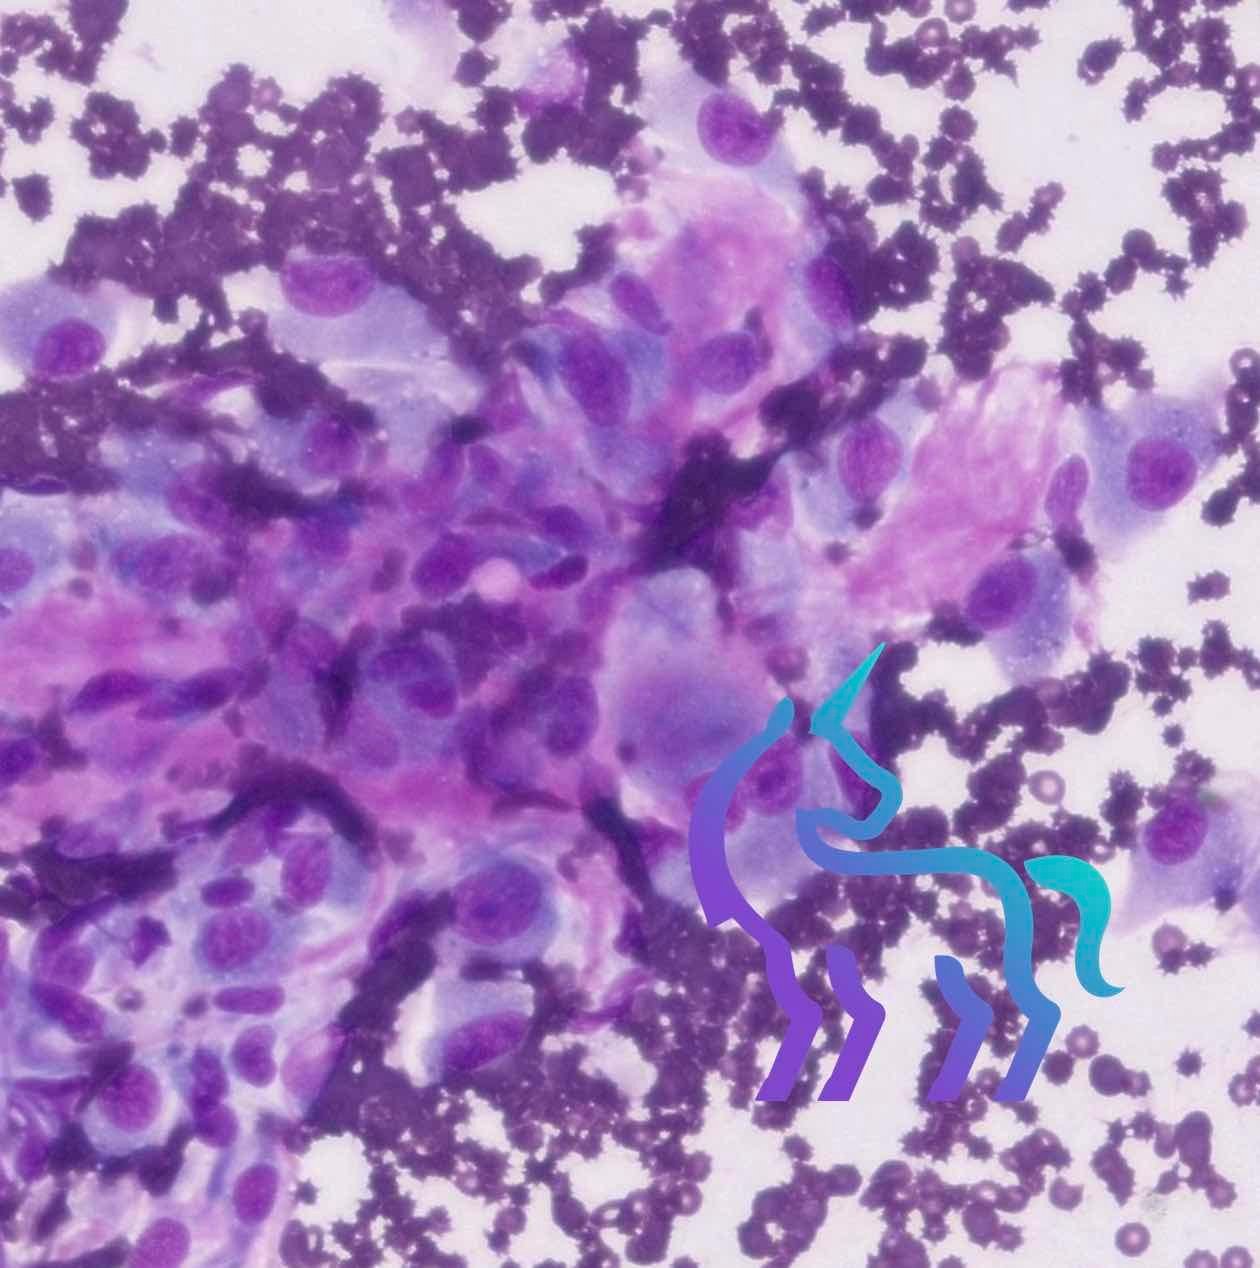

Cytologie et masses : une réponse souvent dans l’heure

Grâce au Vetscan Imagyst, les cytologies de masses, nodules ou ponctions peuvent, dans de nombreux cas, être interprétées dans l’heure. Cela permet d’orienter rapidement la conduite à tenir.